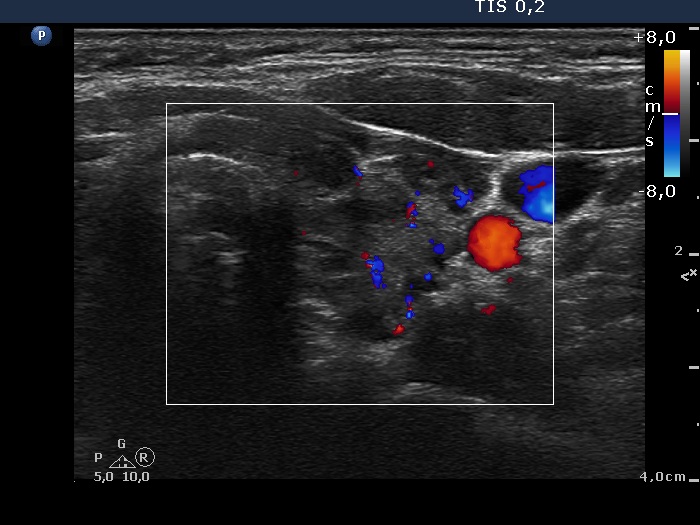

Discrete lesion or nodule in Hashimoto's thyroiditis - case 21 (1496) (ultrasonographic picture 6)

Left lobe, transverse view, color Doppler mode. The vascularization is not specific.